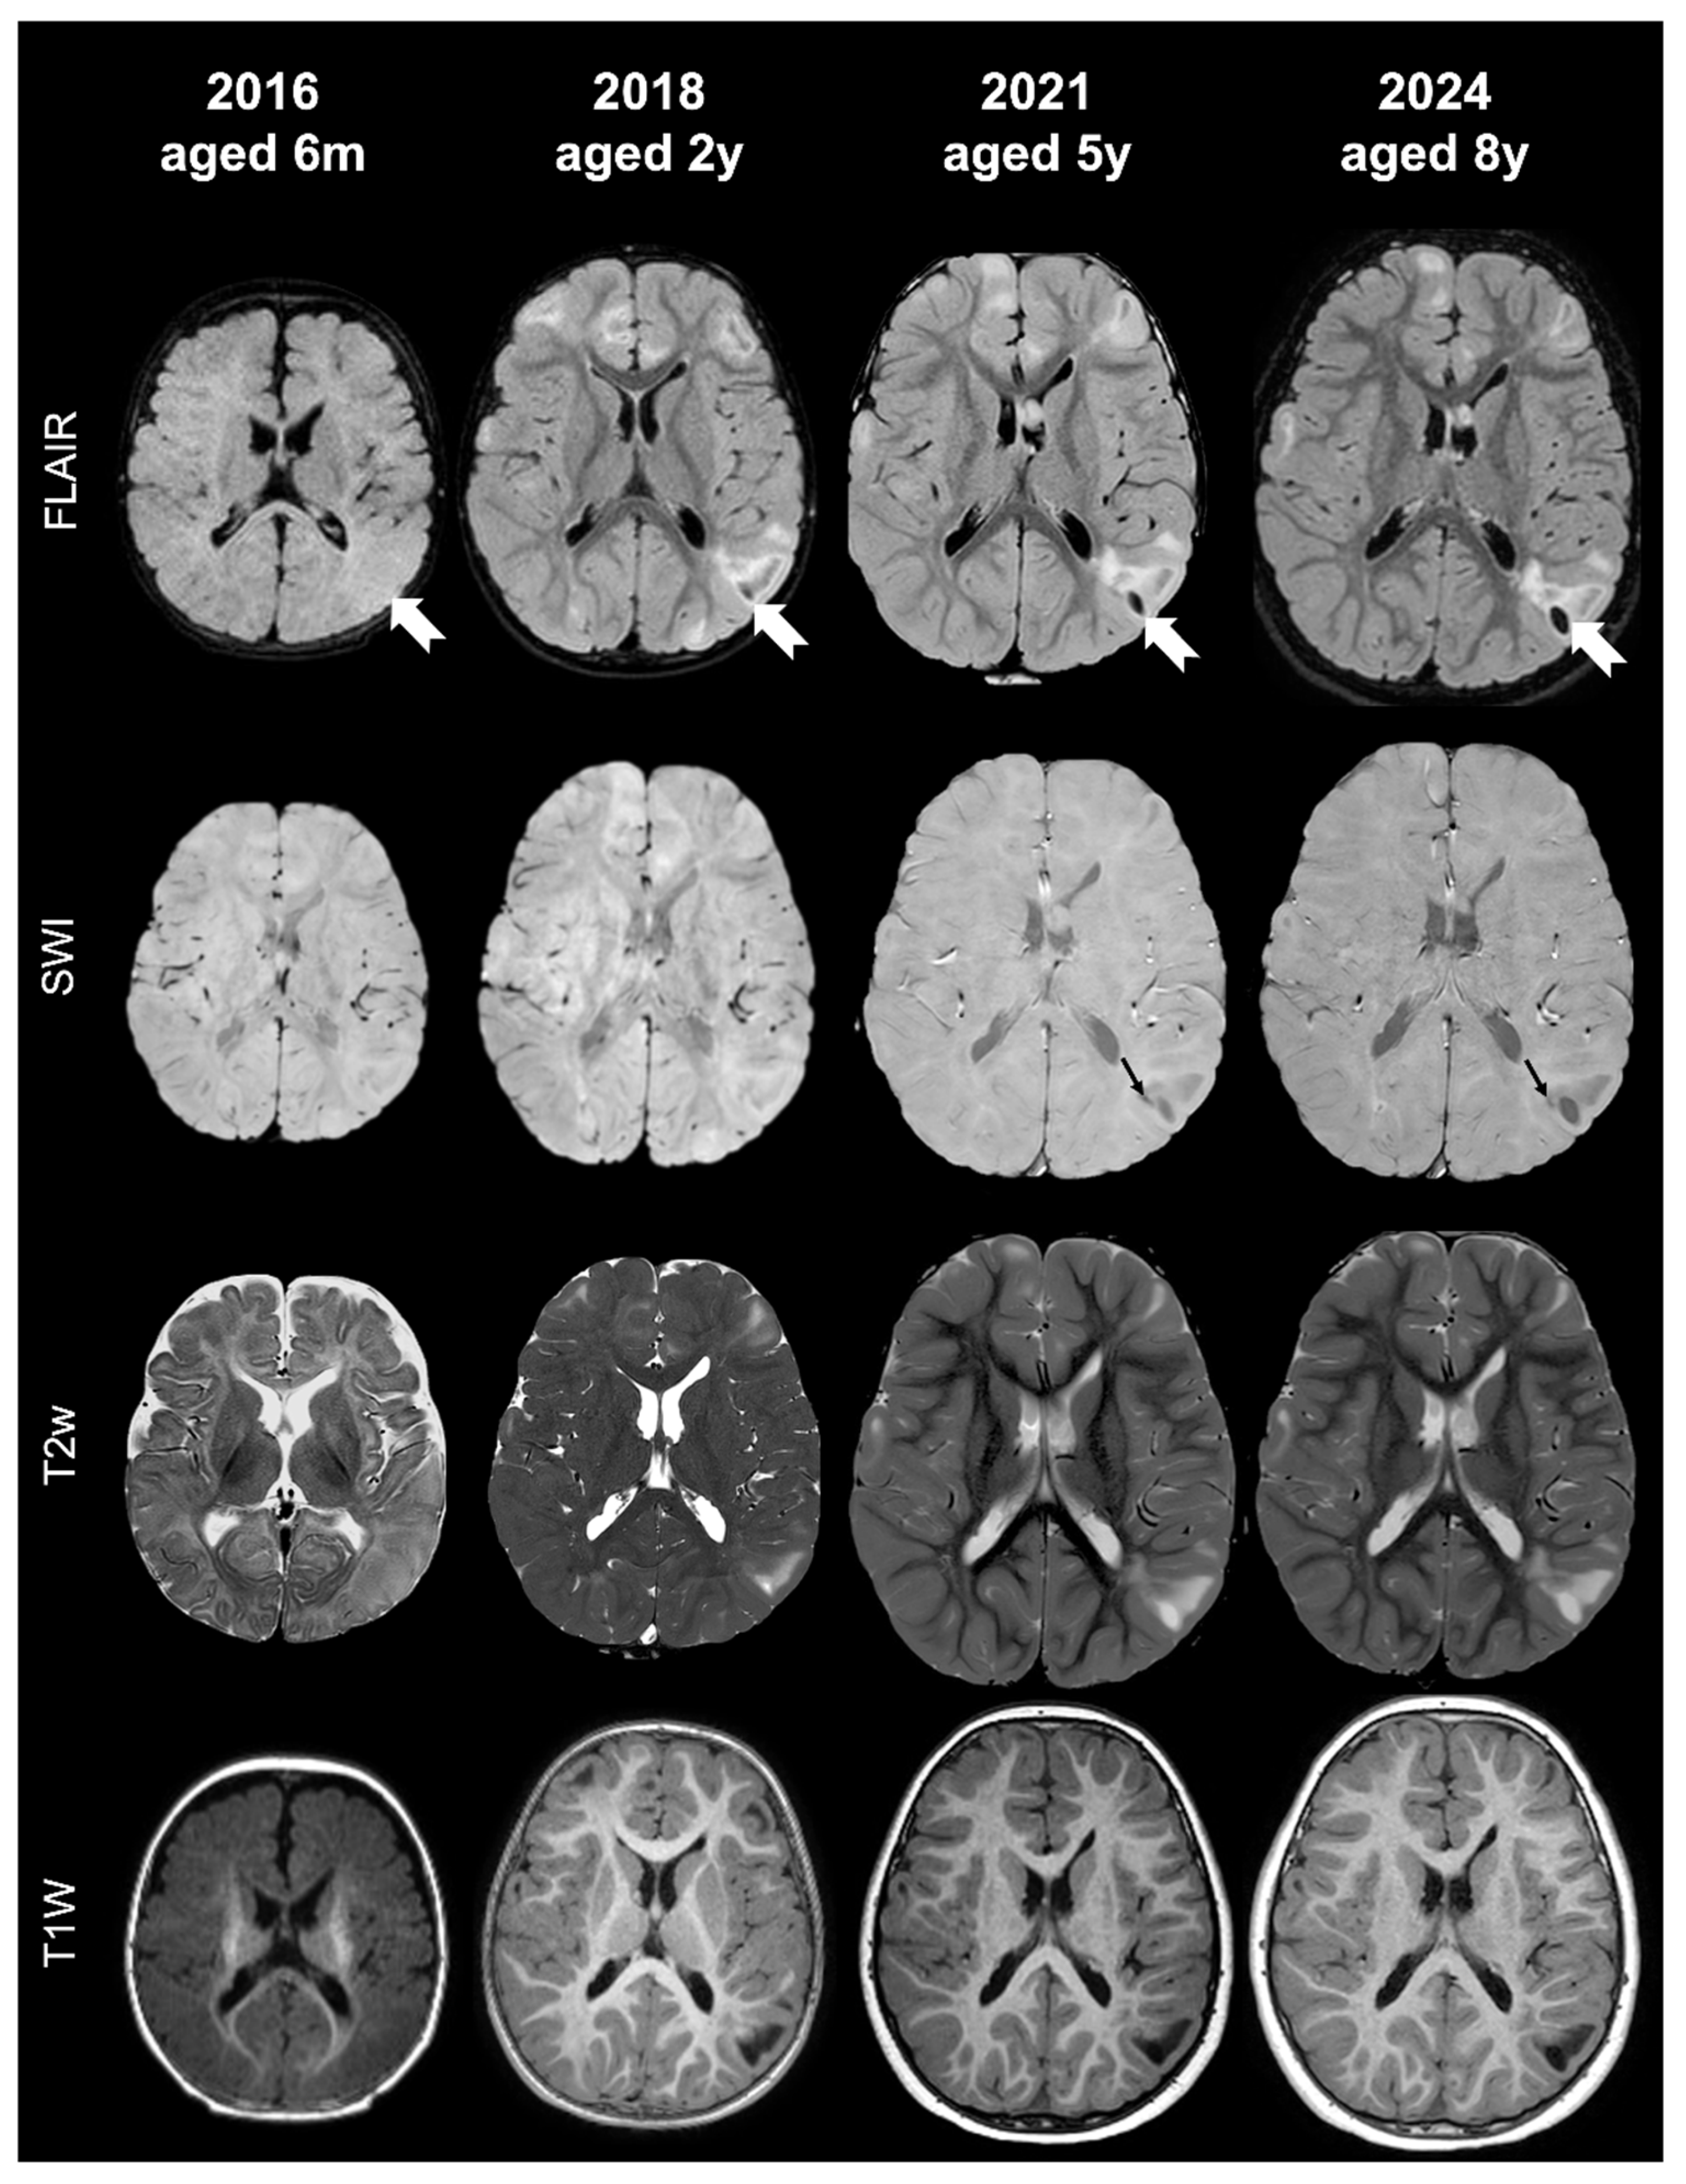

- Tuber A (corresponding to former tuber A in the classification by Gallagher et al., 2010 [27]): isointense on volumetric T1-weighted images and subtly hyperintense on T2-weighted images, with no mass effect, no distortion of the gyral folding pattern, and no calcifications on SWI.

- Tuber B (corresponding to former tuber B in the classification by Gallagher et al., 2010 [27]): hypointense on volumetric T1-weighted images and homogeneously hyperintense on T2-weighted images, with no well-defined borders, minimal mass effect, slight disruption of the gyral pattern, and no calcifications on SWI.

- Tuber C: hypointense on volumetric T1-weighted images and homogeneously hyperintense on T2-weighted images with inner calcifications on SWI, further divided into the following:

- Tuber D: hypointense on volumetric T1-weighted images and homogeneously hyperintense on T2-weighted images with a central cystic area of vacuolization, regardless of the presence of associate calcification(s).

- Tuber A: isointense on volumetric T1-weighted images and subtly hyperintense on T2-weighted images, with no mass effect, no distortion of the gyral folding pattern, and no calcifications on SWI

- Tuber B: hypointense on volumetric T1-weighted images and homogeneously hyperintense on T2-weighted images, with no well-defined borders, minimal mass effect, slight disruption of the gyral pattern, and no calcifications on SWI

- Tuber C1: with subtle, non-confluent, pinpoint-like calcifications on SWI (micro-calcified)

- Tuber C2: with large, confluent, linear or curvilinear calcifications on SWI (macro-calcified)

- Tuber D: hypointense on volumetric T1-weighted images and homogeneously hyperintense on T2-weighted images, with a central cystic area of vacuolization, regardless of associated calcification(s).